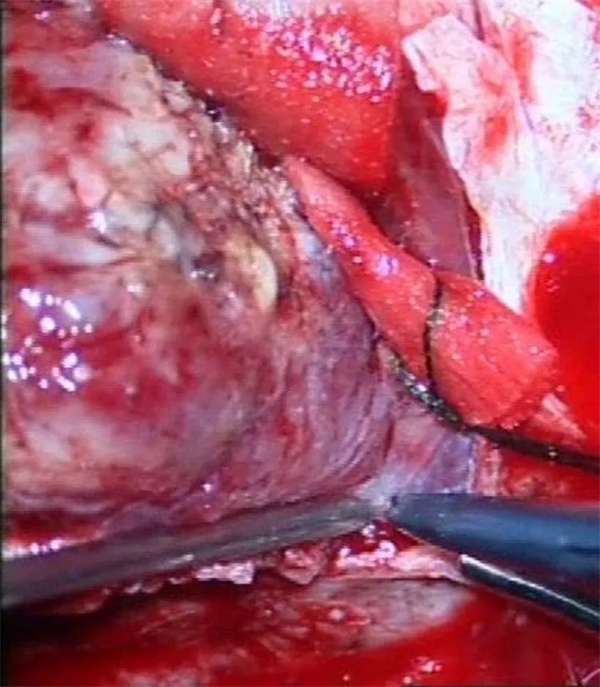

11月28日凌晨一点左右,朱某睡眠正酣,突发四肢抽搐,口吐白沫,双眼上翻,呼之不应,持续数分钟方才停止,睡在一旁的妻子目睹这一切,仿佛经历晴天霹雳,还以为丈夫“被鬼打了” 或“是中邪了”,一时间不知所措。待缓过神后还是拨打120,120把朱某送至捕鱼游戏 神经外科,头颅CT 检查提示右侧顶枕叶类圆形高密度占位,接诊医师姚勇、李世清考虑颅内占位所致继发性癫痫。